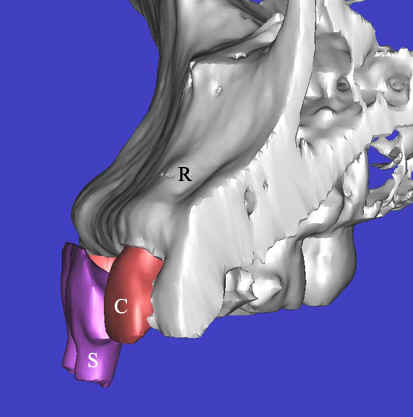

A 43 year-old lady has lost #7 and 8 due to caries for ~ 2 year. It appears that the ridge is wide (Fig.1). To place implants in ideal position, cone beam CT is planned. Models are mounted (Fig.2); diagnostic wax-up is finished (Fig.3). Drill sleeves (arrowheads in Fig.4; 10 mm long, 2.2 mm in diameter; Straumann) are placed lingual to the incisal (I) edges of the neighboring teeth. The position of drill sleeves is confirmed by CT: between the incisal edge and the cingulum (Fig.5). The cross sections at #7, 8 and 9 are shown in Fig. 6, 7 and 8, respectively. However, the long axis of the sleeve (S) or the natural tooth #9 is not aligned with that of the alveolar ridge. This orientation is good from prosthetic viewpoint, but we cannot place a long or wide implant. The lateral view of the three-dimensional image shows that the long axis of the crown (C) of #9 is not in line with that of its root/ridge (R, Fig.9). It appears that the trajectory of an implant should be not decided by wax-up, but should be adjusted to accommodate the morphology of the alveolar ridge. In all, the drill sleeve (S) should be moved and tilted more labially to place the longest and largest implant.